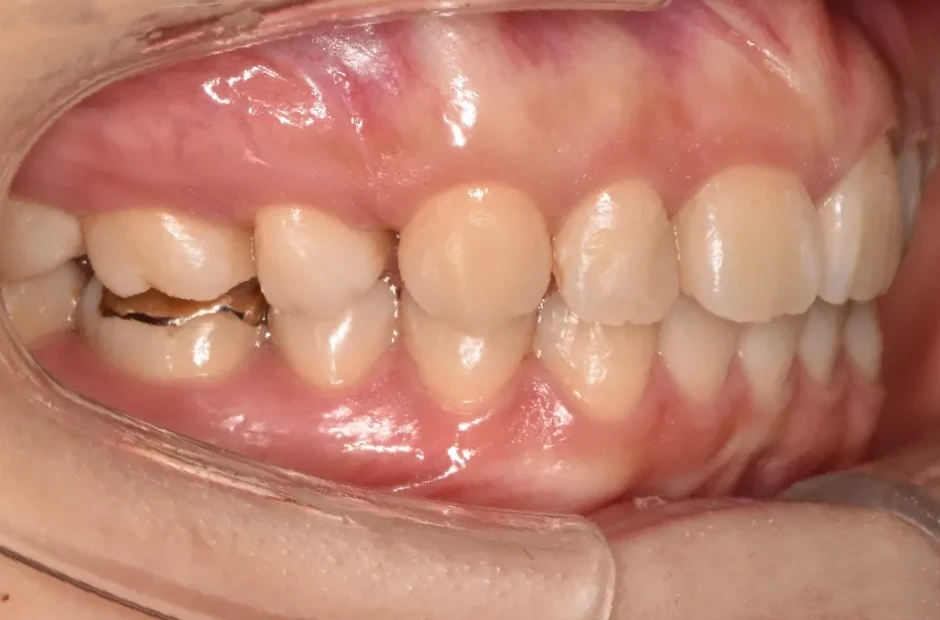

反対咬合

| 診断名・主訴 | 下顎前突、叢生 |

| 年齢・性別 | 23歳・女性 |

| 治療期間・回数 | 3年 |

| 治療に用いた主な装置 | 上顎5,5 下顎4,4 |

| 抜歯部位 | 舌側矯正 |

| 治療費 | 100万円(税抜) |

| リスク・副作用 | 装置による違和感・疼痛・歯肉退縮・歯根吸収・虫歯のリスクなど |

治療後